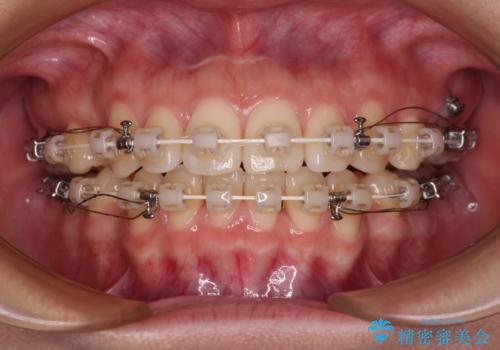

- 審美装置

- 2年6ヶ月

突出感改善のため、上下左右の第一小臼歯4本を抜歯し、ワイヤー装置にて矯正治療を行うこととしました。

舌のトレーニングをしっかりと行ってくださり、予定通りの期間で理想的な仕上がりを達成することができました。